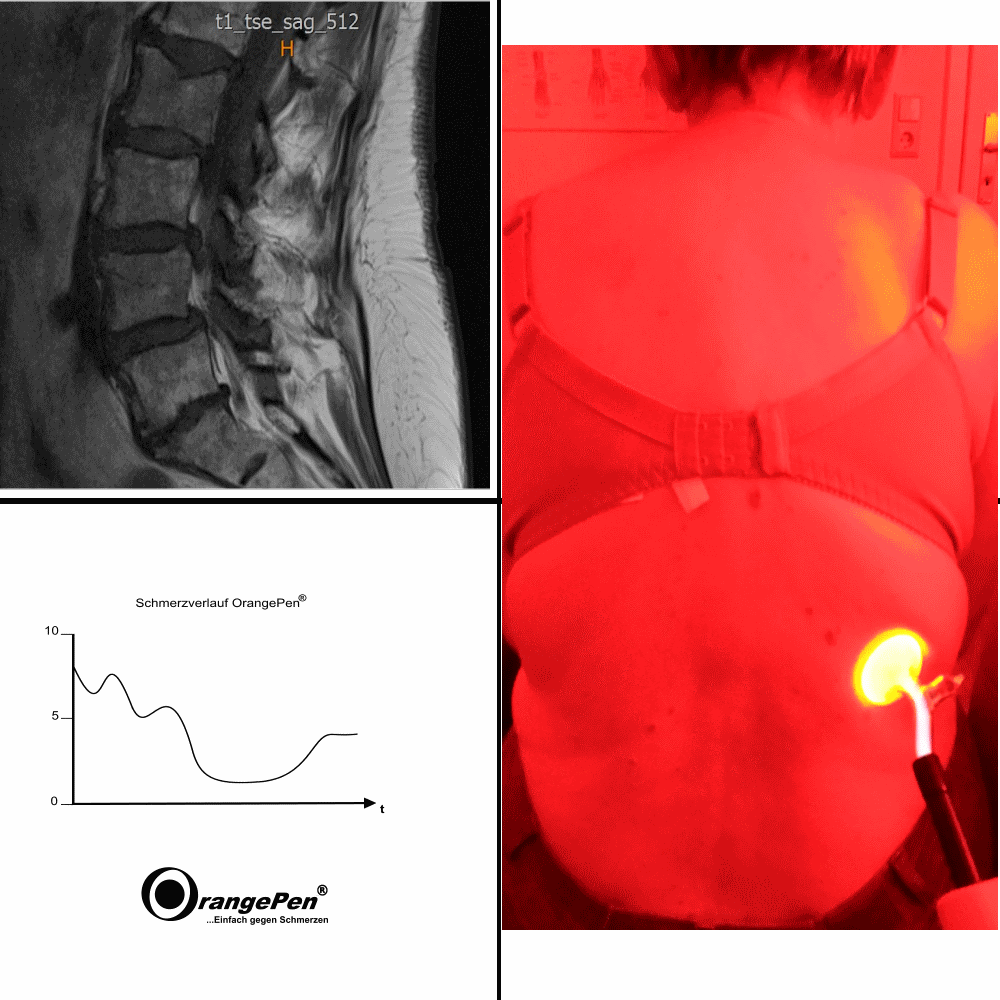

Back pain with recurrence

Back pain with recurrence treated with OrangePenreg;

The patient came to me because she had had difficult to handle back pain for many years. After a few sessions, these were significantly reduced. Unfortunately, the damage is too great, so that aftercare is necessary from time to time. Patient presents herself approx. every 4-8 weeks.